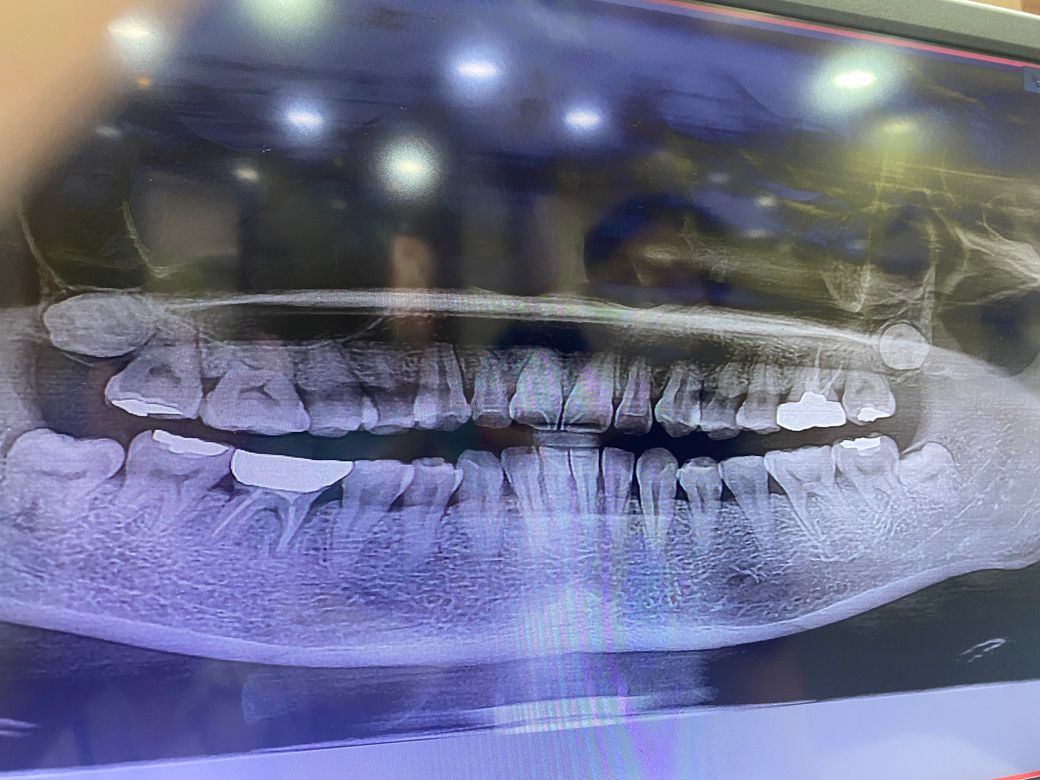

엑스레이로 잇몸 안 충치나 치석도 보이나요??

혹시나 해서 엑스레이도 올려봅니다

-엑스레이

엑스레이상으로는 충치의 여부가 정확하게 보이지는 않습니다.

정확한 확인을 위해서는 해당부위의 치근단 사진이 있으면 도움이 될수 있습니다.

파노라마 사진은 전체적을 치아나 잇몸뼈 상태를 보는거고 충치가 의심되면 작은 사진을 찍어서 확인합니다.

충치에 대한 판단은 저런 큰 엑스레이 사진 말고 작은 해상도 좋은 사진(치근단 사진)이 필요합니다만 언뜻 보기에는 충치의 양상도 있어 보입니다. 애초에 앞니와 옆 치아 공간이 벌어져 있었기 때문에 치태, 음식물이 잘 끼었을 것이고 충치와 치석이 생겼을 가능성이 높습니다.